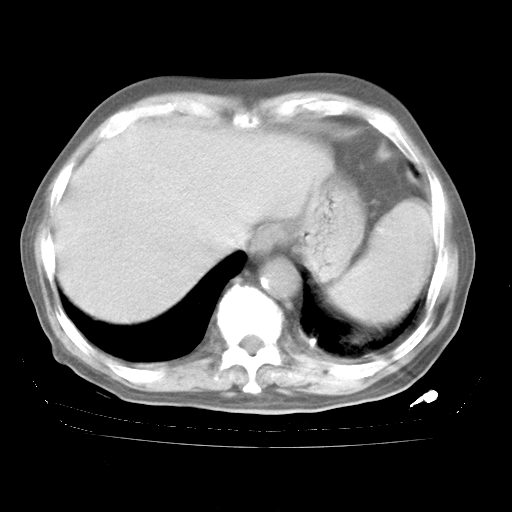

4月28日肺部CT——再次出现类似去年5月9日——透光度降低,“间质性”改变。